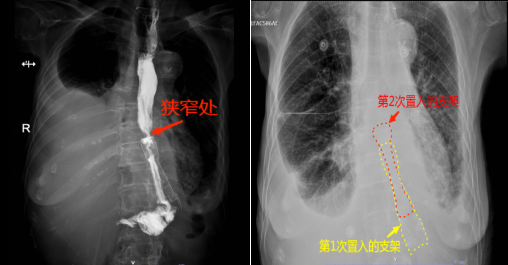

74岁的余婆婆在2013年时因胃癌行全胃切除术,但是从2022年起,她就出现了吞咽困难的情况,期间曾被诊断为食管吻合口狭窄并行内镜下食管金属支架置入术,但仅几个月后又出现了吞咽困难的情况。近期,余婆婆吞咽困难情况加重,滴水不进,身体每况日下,被家人送到湖北省第三人民医院阳逻院区消化内科治疗。消化内科主任金雷接诊后结合CT结果,考虑患者不能进食的原因为食管支架上方狭窄所致。消化道肿瘤术后吻合口肿瘤复发、或者吻合口周围的肉芽组织增生或瘢痕等所导致的吻合口及邻近部位的狭窄,内镜下评估狭窄部的直径<1cm,常伴有不同程度的吞咽困难。为患者完善了上消化道碘水造影检查,果不其然,上消化道造影提示,食管下段近金属支架上端入口水平明显狭窄。此时患者重度营养不良、体重不到70斤,并伴有右侧大量癌性胸水,心肺功能不全。结合患者病情,金雷为其制定了在原有食管支架上方狭窄处再叠加放置一个新的食管支架的治疗方案,重新打通这条“生命通道”,恢复患者进食,改善患者生存质量。

通过加强肠外营养支持,多次穿刺抽取胸腔积液改善肺功能后,患者精神、体力较入院时已有改善,符合手术指征。进行充分的术前准备后,金雷在消化内镜中心顺利为余婆婆进行了“内镜下食管狭窄球囊扩张术+覆膜金属支架置入术”。术后复查胸片,新放置的金属支架成功跨过狭窄处与原有金属支架上端相叠加,原本狭窄的食道再次畅通无阻。在消化内科医护专业的指导和精心的护理下,余婆婆再次品尝到了久违的食物,术后第二天即恢复了半流质饮食,吞咽顺畅再无梗阻感。目前患者恢复良好,已经顺利出院。